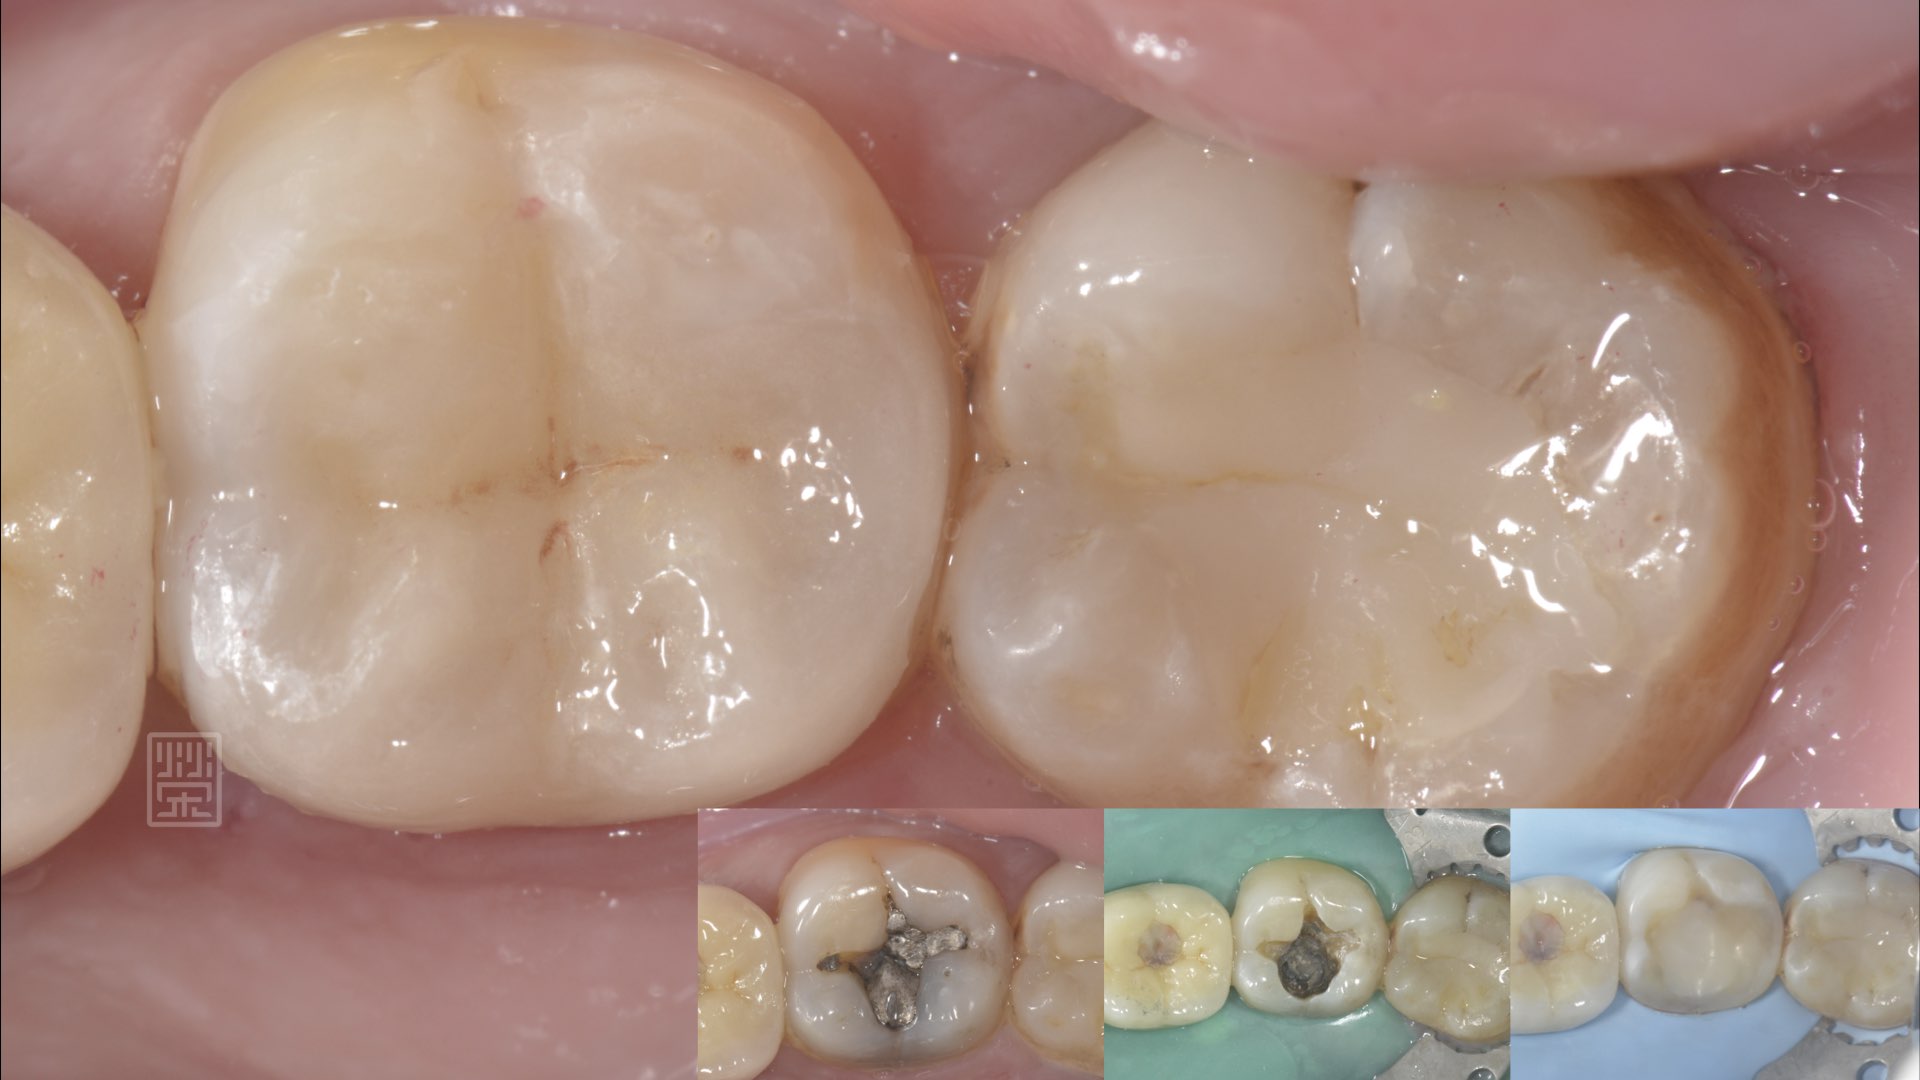

全瓷嵌體修復